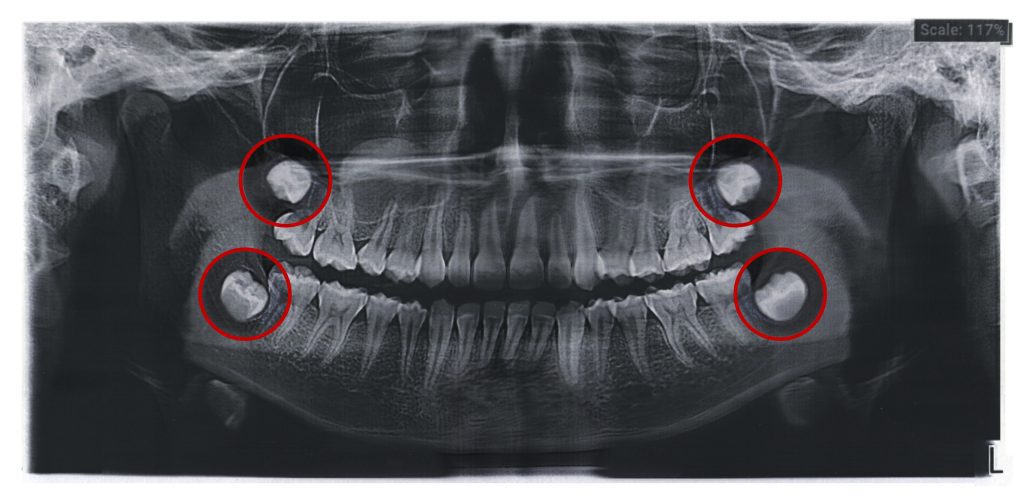

Las muelas del juicio son los últimos dientes en aparecer. Estos terceros molares, ubicados en las cuatro esquinas de la boca, pueden generar dolor, inflamación o infecciones si no tienen el espacio suficiente para salir de manera correcta. Con el paso del tiempo, las muelas del juicio han perdido su función original: ayudar a triturar […]